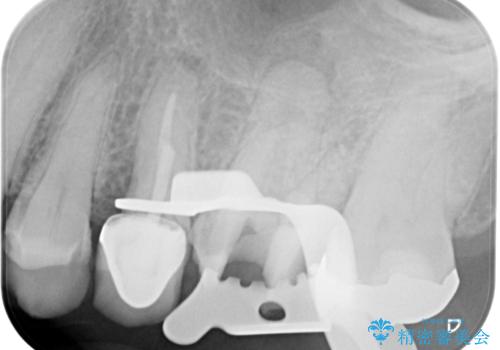

【破折ファイル除去】他院で折れた根管治療の器具をとってほしい

- 他院で折れた根管治療の器具をとってほしいという主訴で来院されました。

マイクロスコープで根管内を観察すると、除去できる状態だったため破折ファイル除去を行いオールセラミッククラウンにて修復治療しております。

通常、根尖湾曲の先にあるファイルは無理に取るより外科治療によりアプローチすることを推奨しています。